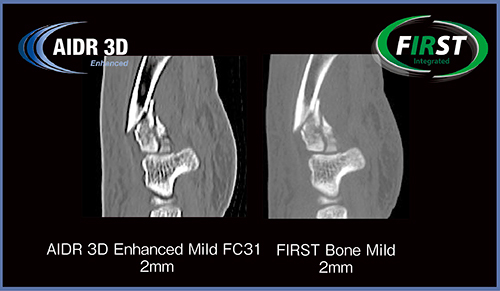

整形領域の骨折症例において,AIDR 3D Enhancedでは硬い再構成関数を用いるため骨周辺のアンダーシュートが目立つが,FIRSTでは認められず,骨皮質の評価や微細な骨折,骨片の描出能が高い(図1)。骨折部位のプロファイルを取ったところ,FIRSTではアンダーシュートがないことが確認できた。

図1 骨折症例におけるAIDR 3D EnhancedとFIRSTの比較